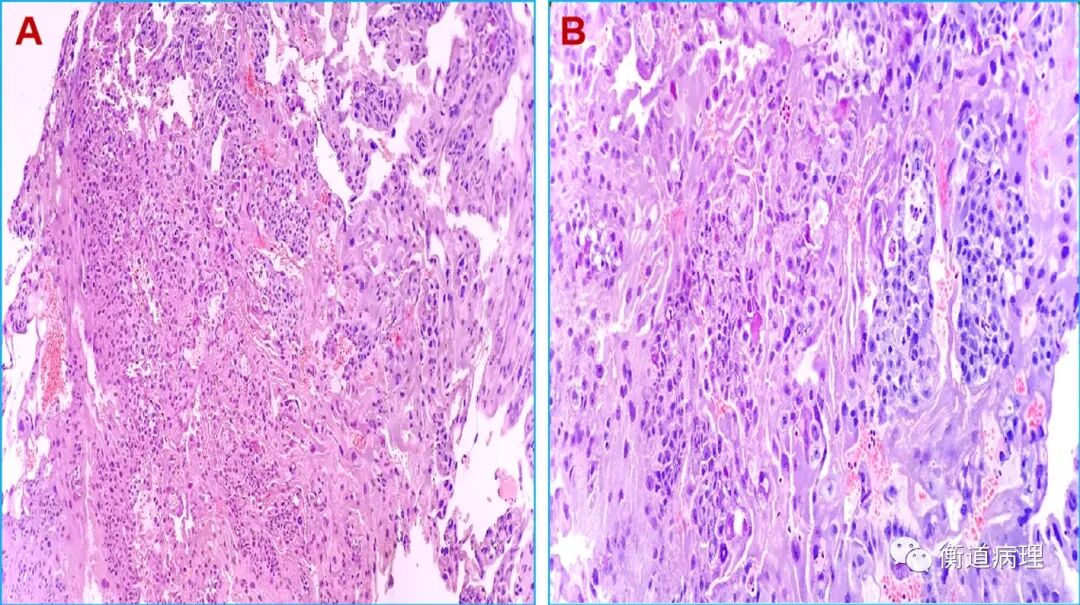

#国民医生说##健闻登顶计划##微博热点优质创作计划# 畸胎瘤是怀了“怪胎”吗?和胚胎发育有关吗?畸胎瘤并不是怀了 “怪胎”,它本质上是一种生殖细胞肿瘤,和正常胚胎发育没有直接关联,这是一个极易引发误解的医学概念。从病理本质来看,畸胎瘤是由胚胎时期的生殖细胞异常分化形成的肿瘤,而非真正的 “胎儿”。生殖细胞本应分化为人体的各类组织器官,但在发育过程中,部分细胞脱离了正常的分化轨道,在卵巢、睾丸等部位异常增殖,最终形成包含多种组织成分的肿瘤 —— 它可能含有毛发、牙齿、骨骼、油脂甚至少量神经组织,这些只是分化紊乱的人体组织,并非完整的胚胎或 “怪胎”。关于和胚胎发育的关联,需要区分两个层面:一方面,畸胎瘤的起源确实和胚胎阶段的生殖细胞有关,其发病根源是胚胎期生殖细胞的分化异常;但另一方面,它和母体的正常妊娠、胚胎孕育没有任何关系,既不是母体怀孕时形成的 “异常胎儿”,也不会因为怀孕而诱发或加重,未婚未育人群也可能患上畸胎瘤。另外,畸胎瘤多数为良性(成熟畸胎瘤),少数为恶性(未成熟畸胎瘤),良性畸胎瘤通过手术切除即可治愈,恶性类型则需结合病理分级进行后续治疗,总体预后相对较好,无需因 “畸胎” 的名称产生过度恐慌。